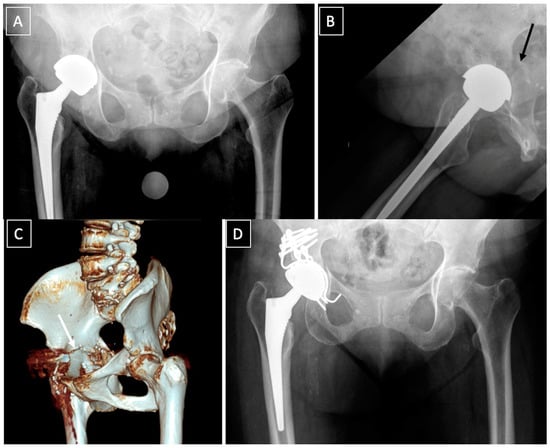

- Acetabular distraction was first described by Sporer et al. in 2012 [53]. The acetabulum is reamed until the antero-superior and postero-inferior margins are engaged. Remaining bone defects are filed with porous tantalum augments. An acetabular component of the same material, 6–8 mm larger than the last reamer is then impacted. The distraction creates a press fit and a pelvic recoil as a result of ligamentotaxis [54]. The latter in conjunction with multiple screws inserted in the remaining ilium and ischium provides initial stability. The polyethylene liner or a dual mobility cup is then cemented into the shell [53]. Although relatively new, acetabular distraction is a promising treatment for chronic PD. Excellent results [40,42,53,55], with low complication rates, 3–5% aseptic loosening [40,53], have been reported at 2- to 7-year follow-up.

- Custom-made triflange implants are another option to address chronic PD with severe bone loss. Based on a preoperative CT scan, an individually produced titanium, porous and/or hydroxyapatatite-coated triflange cup is made. Through the fixation of the three flanges (ilial, ischial and pubic), initial stability with the hip COR in anatomic position can be achieved. Excellent results and >80% survivorship of the implants are reported [42,56,57,58]. The disadvantages of this implant are high costs, long manufacture time (6 weeks) and the high rates of dislocation, up to 21% [42,56,57].